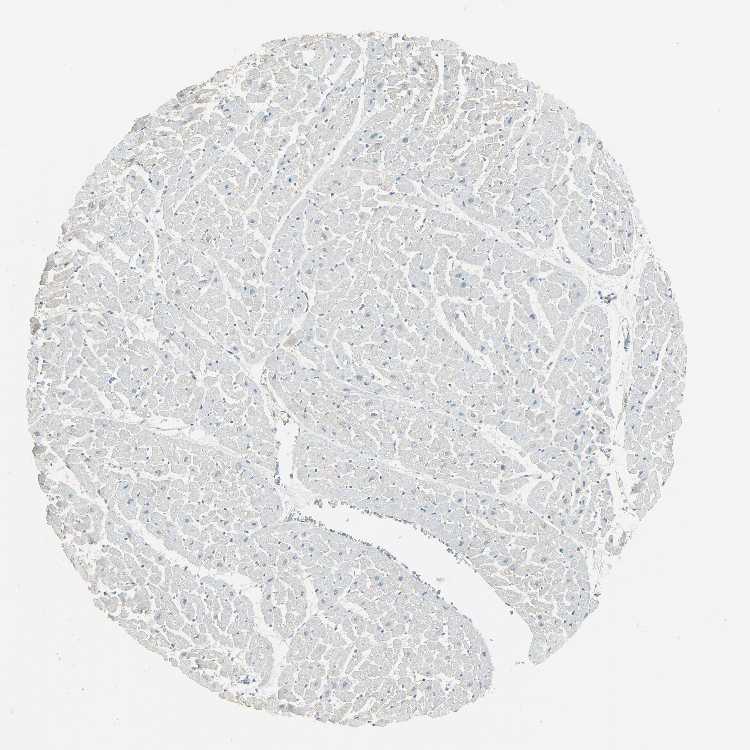

HEART MUSCLE - Antibody stainingi

Antibody staining in the annotated cell types in the current human tissue is reported as not detected, low, medium, or high, based on conventional immunohistochemistry profiling in selected tissues. This score is based on the combination of the staining intensity and fraction of stained cells.

Each image is clickable and will lead to virtual microscopy that enables deeper exploration of all samples and also displays staining intensity scores, fraction scores and subcellular localization as well as patient and tissue information for each sample.

Antibody HPA005525Antibody HPA064708Antibody CAB012459

Cardiomyocytes Not detectedMediumNot detected